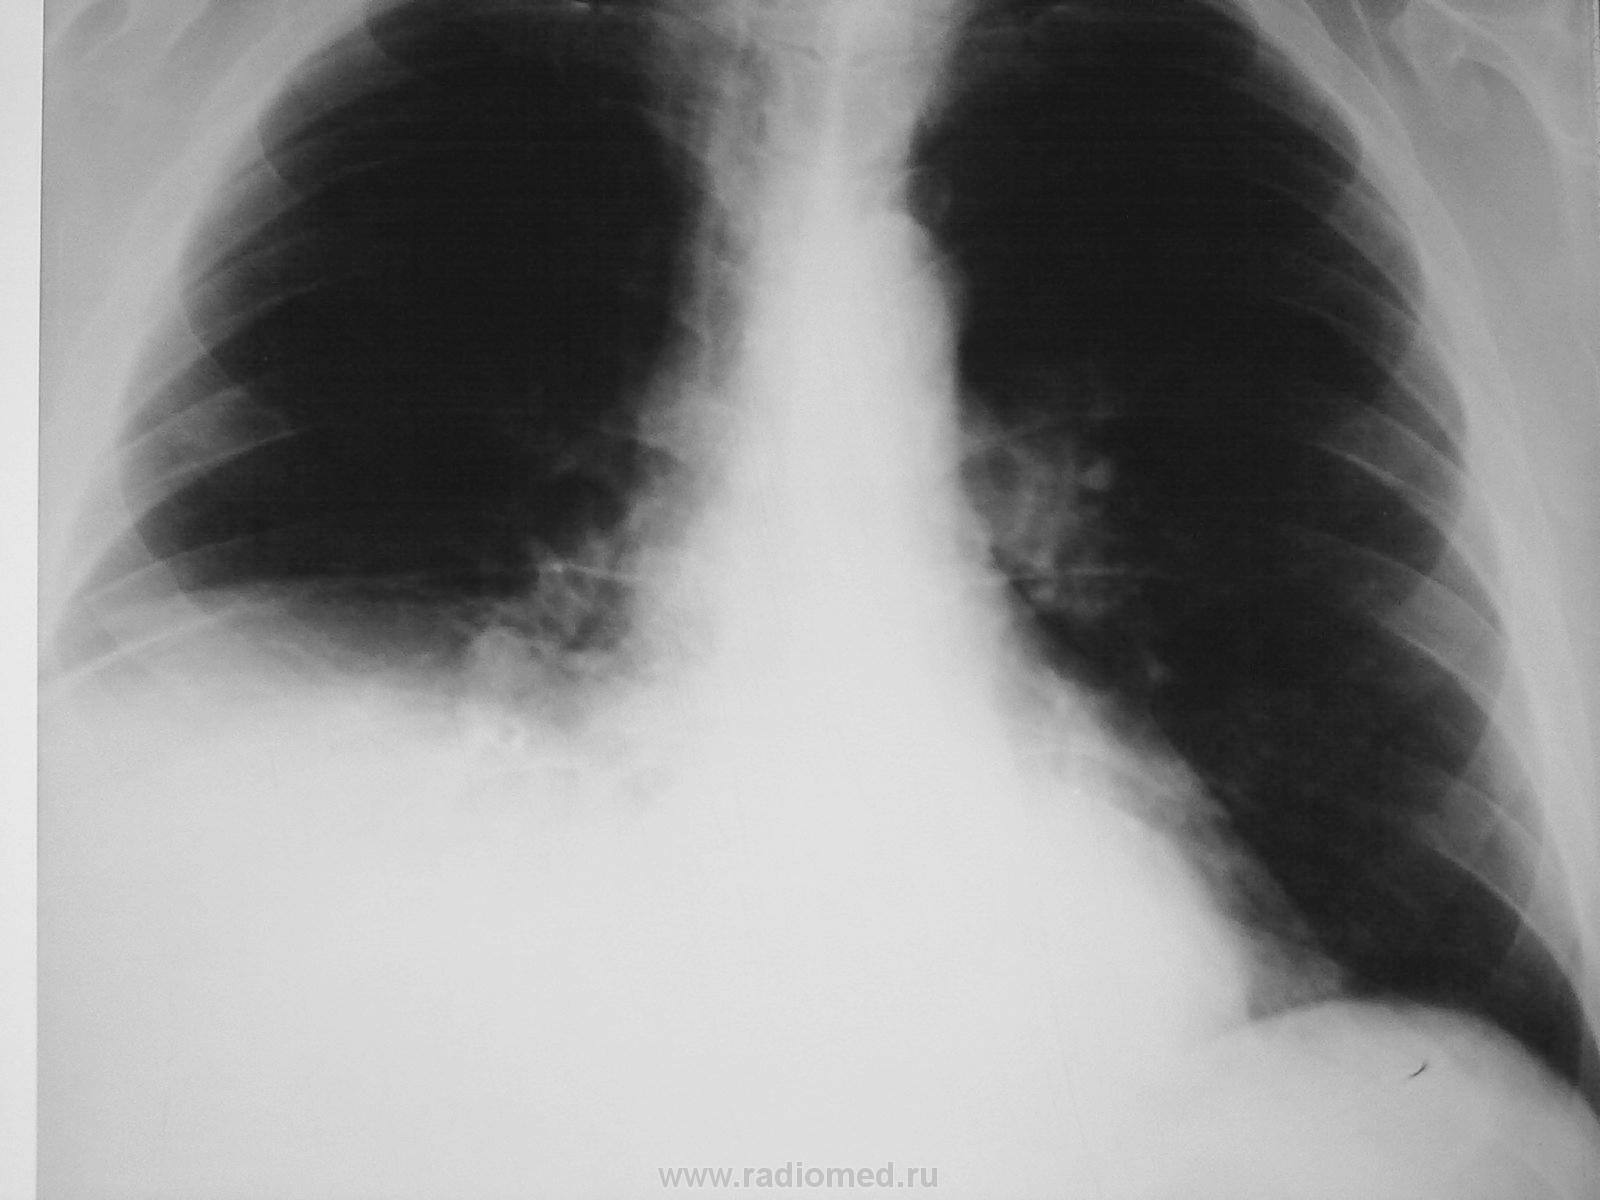

пациент поступил в терапию с подозрением на пневмонию, на третий день заболевания с температурой 38, кашель. УЗи брюшной полости - без патологии. о чём можно думать?

Периферическое объемное образование? Выпот?

Объемное образование

P.S. Эхинококк печени может.